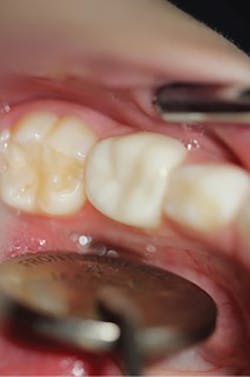

The steps for preparation and cementation were as follows. First, local anesthesia was delivered. Second, isolation was achieved with an isolation system (Isodry). Third, preparation steps were undertaken: Occlusal preparation was completed using a high-speed handpiece with copious amounts of water and a coarse, long-tapered diamond bur (NuSmile) to achieve an occlusal reduction of 1.5–2 mm. Circumferential reduction of approximately 15–20% was carried out using the same bur. In order to visualize the completeness and evenness of the preparation, a full circumferential reduction supragingivally was completed at this stage. A subgingival preparation was again completed using a high-speed handpiece with copious water and a finer, more tapered diamond bur (NuSmile). As required, a full subgingival reduction to approximately 1.5 mm depth was achieved, ensuring no ledges and a smooth featheredge margin (figure 2). It was essential that the crown fit passively and be able to be seated completely unencumbered. In order to ensure fit and occlusion and to prevent contamination of the zirconia crown to be cemented, a Try-In crown (NuSmile) was used (figure 3). Refinements to the preparation to facilitate fit and occlusion were done at this point.

Figure 2: Full subgingival reduction to approximately 1.5 mm depth